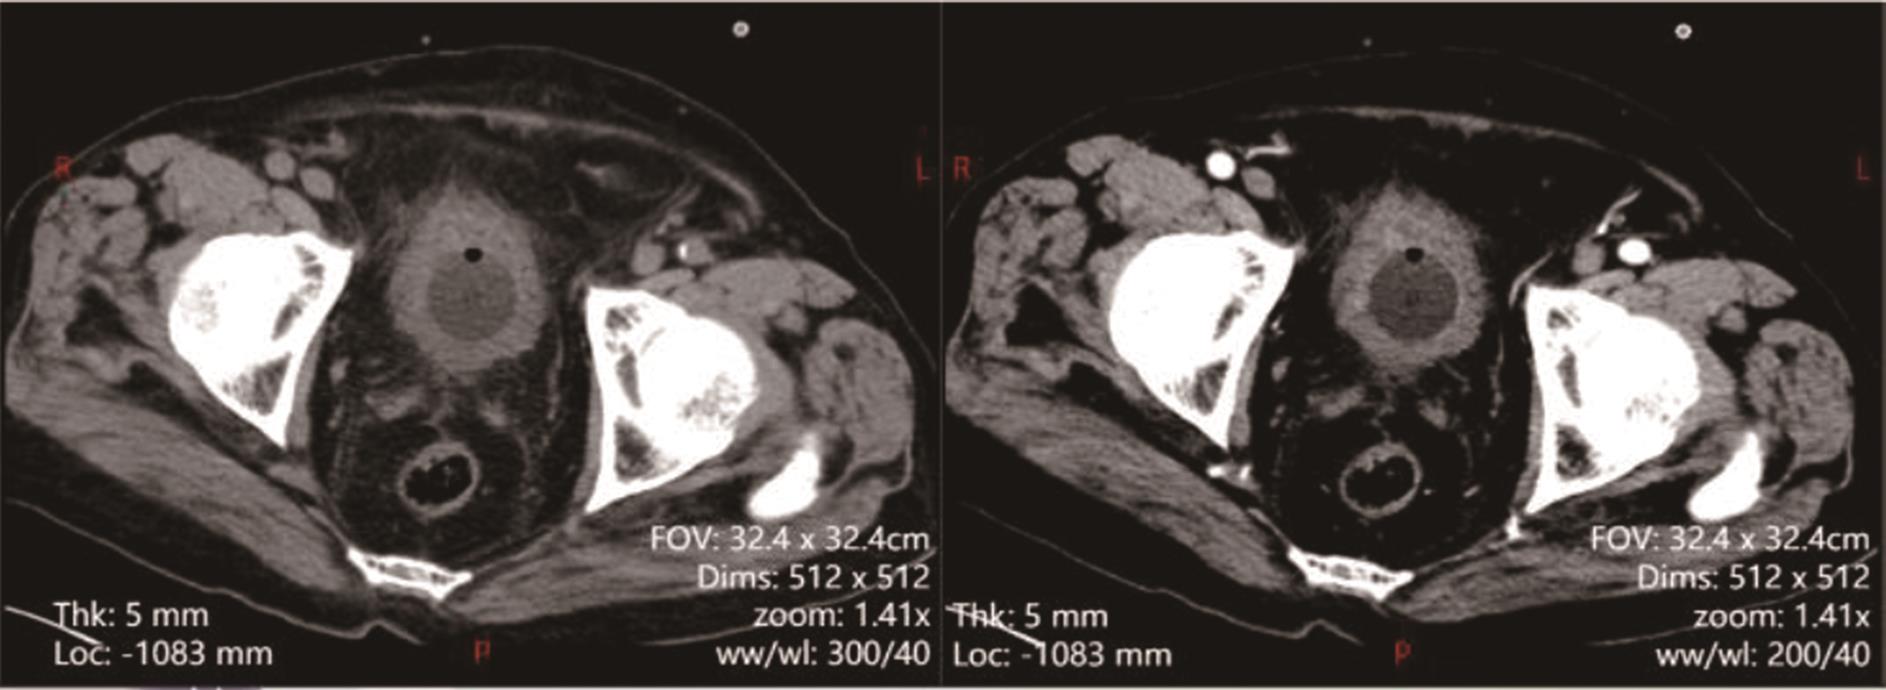

• 转移性上尿路上皮癌在维迪西妥单抗联合替雷利珠单抗新辅助治疗后行根治性肾盂癌切除术1例报道

2023, 48(8):1005-1008. DOI: 10.13406/j.cnki.cyxb.003299

摘要 (52) HTML (36) PDF 2.16 M (1929) 评论 (0) 收藏

摘要: